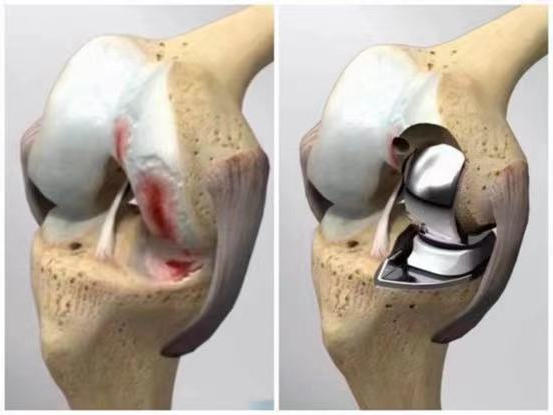

▲膝关节单髁置换示意图

膝关节单髁置换手术,顾名思义,就是仅对膝关节中的某一侧(内侧或外侧)进行置换,以恢复关节功能、减轻疼痛。与传统的全膝关节置换手术相比,单髁置换手术具有创伤小、恢复快、手术外表美观等优点。